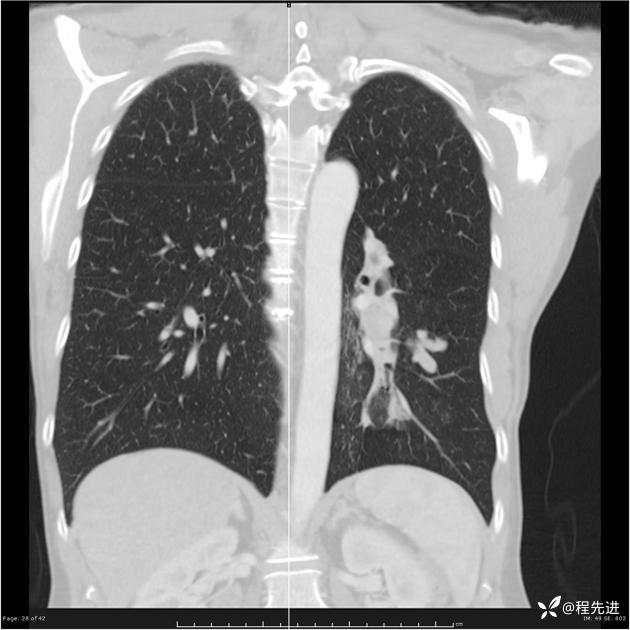

病例女,53岁,气管、左主支气管、下叶支气管内结节,乳头状瘤?期待你的精彩解读

女,53岁

乳头状瘤?